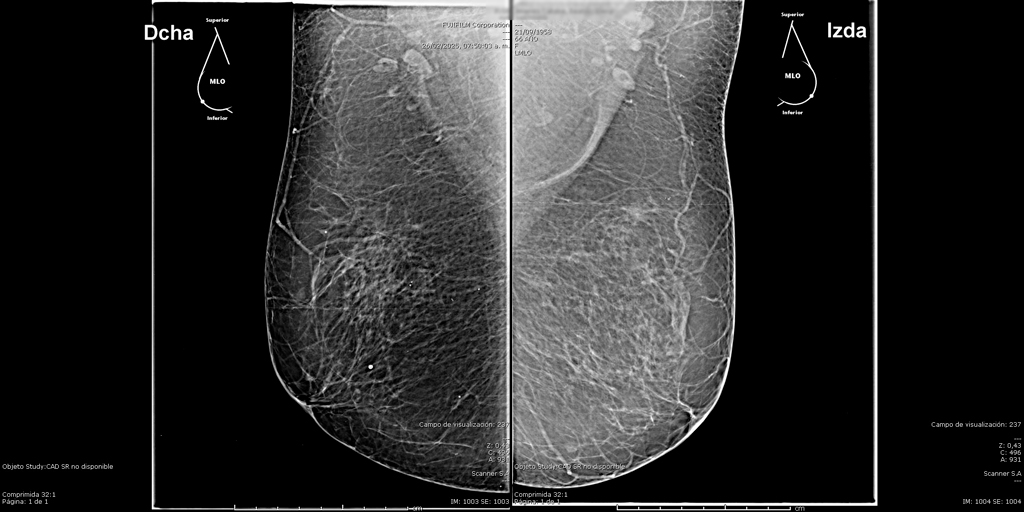

Mamografía Digital

La mamografía es un estudio de diagnóstico por imagen que utiliza bajas dosis de rayos X para obtener imágenes detalladas del tejido mamario. Es una herramienta fundamental para la detección temprana del cáncer de mama y otras patologías mamarias, incluso antes de que sean evidentes al tacto o generen síntomas. Su uso regular en controles preventivos permite salvar vidas al facilitar diagnósticos oportunos y tratamientos más efectivos.

En SCANNER S.A, nuestros equipos digitalizados permiten detectar cambios mínimos en el tejido mamario con alta claridad, permitiendo asi tener un diagnostico preciso y entregar unos resultados reales a nuestros pacientes.